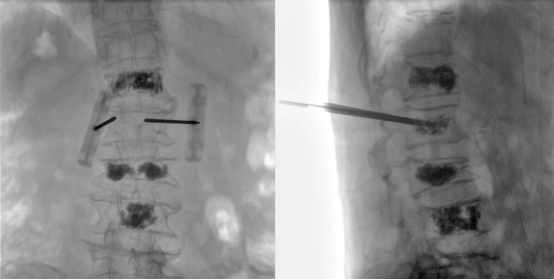

Recently, with the assistance of the Perlove Medical's all-in-one FPD C-arm, a hospital successfully performed a multi-segment percutaneous kyphoplasty (PKP).

Surgeons face multiple challenges during multi-segment PKP procedures. Accurate localization of the affected vertebrae places higher demands on the imaging field of view and clarity of the C-arm. Because multi-segment PKP require a longer operating time to treat multiple vertebrae, the extended duration not only increases the patient’s physical burden and anesthesia risk, but also raises the likelihood of postoperative complications, such as surgical site infections. Therefore, the ease of operation and efficiency of the intraoperative imaging equipment are equally crucial for surgical success.

The Perlove Medical All-in-One C-arm with a Large Flat Panel Detector features a 30 cm × 30 cm field of view, allowing a single exposure to cover the entire affected vertebral region.

This enables surgeons to comprehensively observe the injured and adjacent vertebrae at once, without repeated positioning or multiple exposures.

It enhances surgical efficiency and accuracy, while reducing the patient’s radiation dose throughout the procedure and saving valuable operation time.